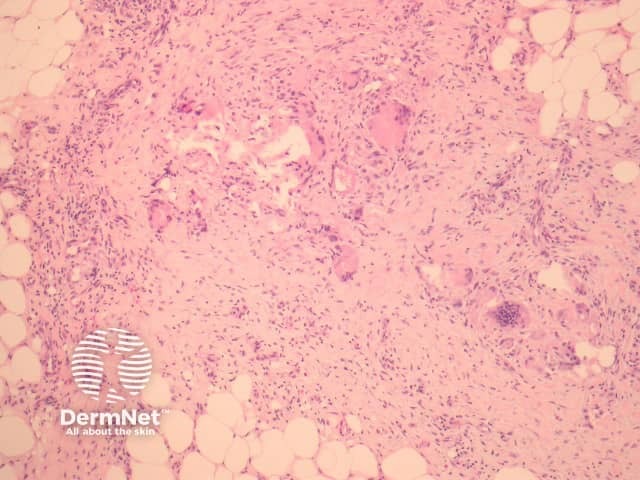

Miescher's radial granulomata that consist of small nodules composed of spindle to oval-shaped histiocytes arranged around minute slits are thought to be a relatively specific finding for erythema nodosum (figure 4).

Figure 3